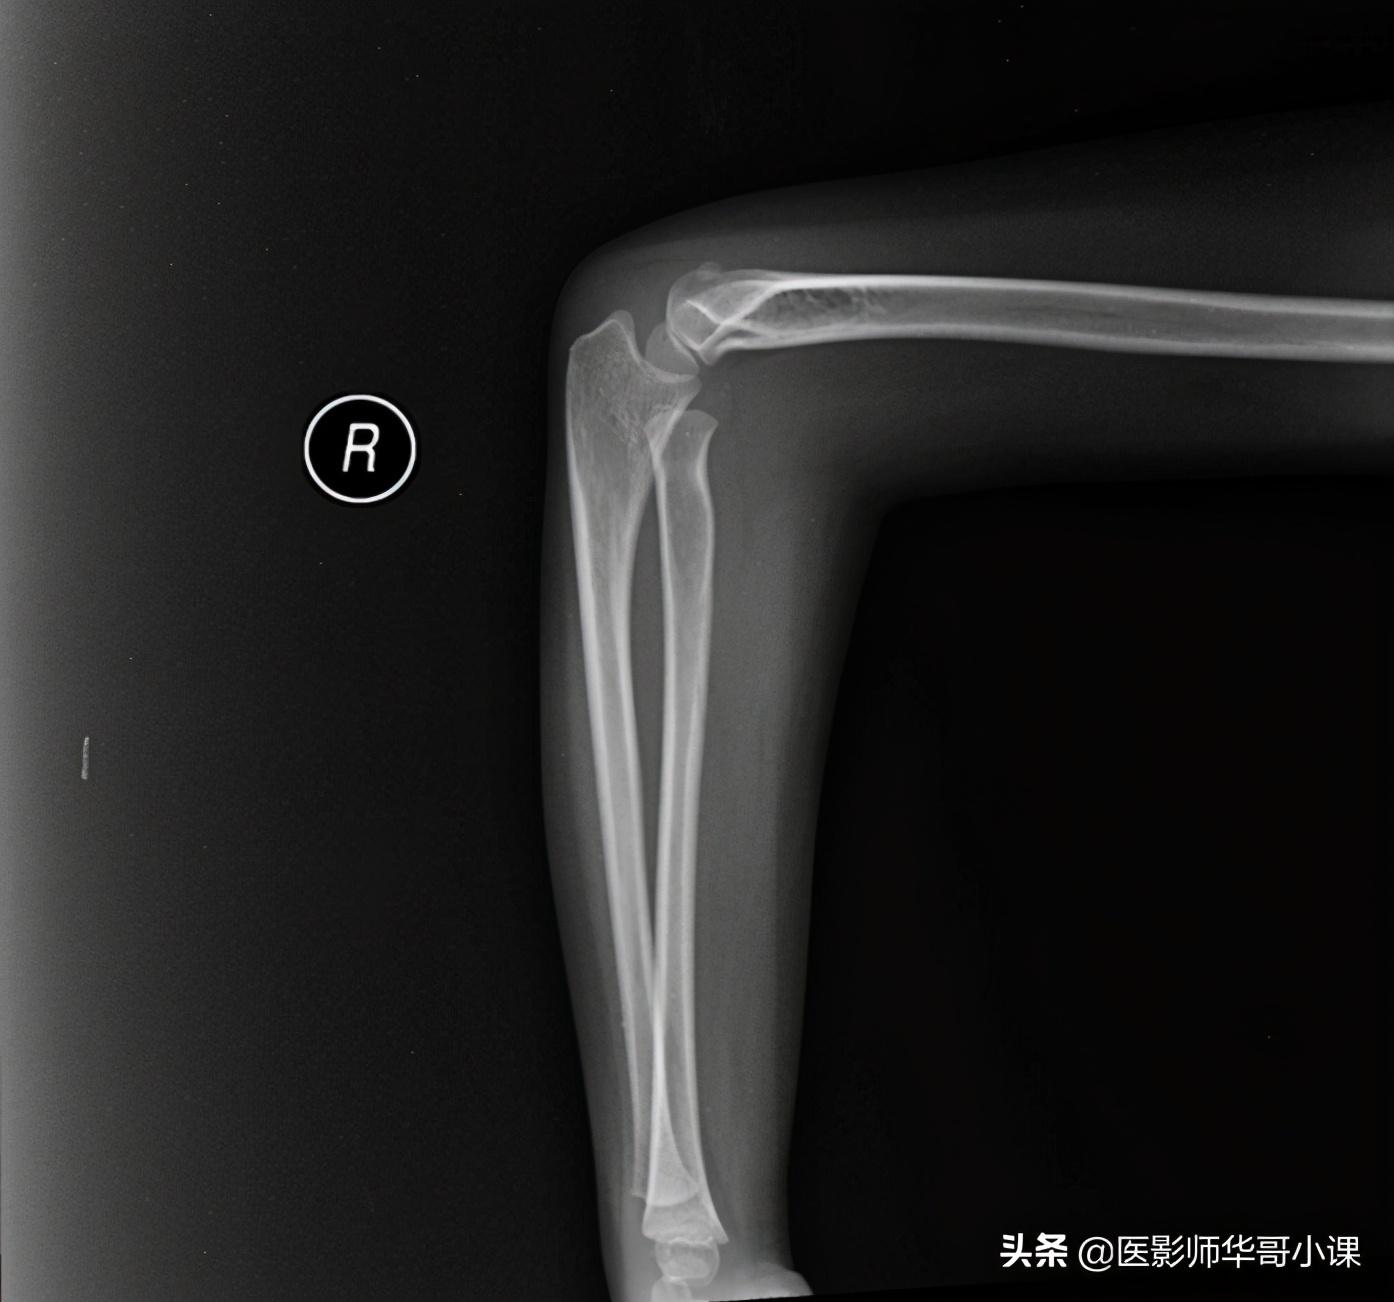

第二节 前臂与肘

桡骨粗隆(结节)的皮质较薄,海绵骨较多。在轻度旋前位时粗隆(结节)和骨干重叠,表现为圆形透明区,颇似空洞;

2.尺骨近端海绵骨较稀疏,呈网状,不可视为骨破环。

3.尺桡骨骨干中1/3处的骨嵴有时凸出,形成边缘致密的阴影,勿误为皮质增厚。

4.平行于尺骨内缘而上行至肱骨内上髁区,有一软组织影,即尺侧腕屈肌的阴影。

5.肱骨鹰嘴窝的骨壁有时很薄,在正位片上显得比较透亮,有时甚至骨壁缺如而成为一个空洞,叫“滑车上孔”。发生率为4%,有遗传因素。

6.成人肱骨髁上嵴,由于肌肉的附着,故正位片上显示边缘粗糙不整。

7.正常肱骨小头的化骨核略靠前,在侧位片上,它与干骺端之间有一定的距离,二者的关系随年龄和投照位置不同而有很大的差异,有时甚至难以肯定肱骨小头化骨核是否有移位。

8.肘部化骨核最为复杂,在诊断骨折和骨骺分离时应十分谨慎,必要时可照对侧比较,肱骨滑车化骨核常为不规则的多个小化骨核,尺骨鹰嘴化骨核亦可为多个,并且边缘不整齐,桡骨和肱骨的化骨核偶尔亦不规则。

9.肘部可以有一些较少见的副小骨,如肘前骨,滑车旁骨和喙状副骨。

10.肘髌骨为一罕见的肘部发育异常,系尺骨鹰嘴二次化骨核未与尺骨融合,遗留在肱三头肌腱内的一种子骨,位于肘关节后方,类似髌骨的骨块,往往与肱骨下端和尺骨鹰嘴相关节。

11.尺骨外形的正常变异,尺骨鹰嘴窝切迹为局限性骨凹,尺骨喙突突起为局限性骨突。